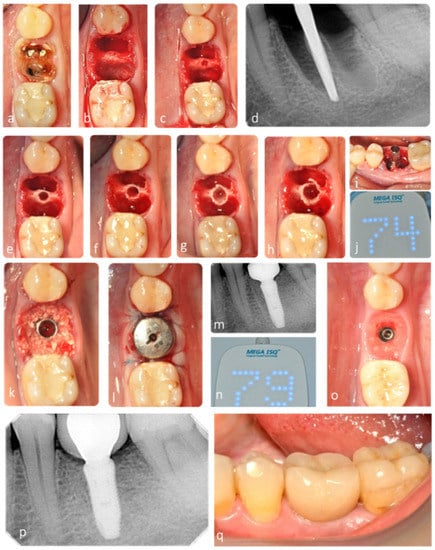

Traditionally, Smith and Tarnow classification type B sockets [] with narrow septa are commonly managed by clinicians through the placement of an immediate implant into the palatal root socket of maxillary molars or into one of the two mandibular molar root sockets []. However, this may lead to potential food impaction and tissue inflammation, due to poor emergence profile of the restoration. Furthermore, Smith et al. [] observed, in a retrospective study of 300 implants, that there is a direct correlation between the horizontal implant–tooth distance and the incidence of adjacent tooth decay. Therefore, immediate implant placement in the mesial or distal molar root sockets may significantly increase the risk of decay in the furthest tooth. Accordingly, the ideal implant positioning in molar sockets will most often require the osteotomy to be in the septum. Osseodensification may facilitate the preservation and the expansion of the interradicular septum, thus enhancing the ability to predictably place implants with adequate stability in both type B and C sockets, as shown in this study (Figure 9).

Figure 9.

Representative clinical case with 4-year clinical and radiographic follow-up. (a) Initial radiograph with 4 mm of residual alveolar bone height. (a) Clinical situation at baseline. (b) Occlusal view after gentle tooth extraction with maintenance of interradicular septum. (c–h) Septum expansion after sequential instrumentation with osseodensification. (d) Radiograph of densifying bur VT1525 (2.0) in interradicular septum. (i,j) ISQ measurement after implant placement (primary stability). (k–m) Grafting of the gap and socket sealing with large healing abutment. (n) ISQ measurement after osseointegration period (secondary stability). (o) Contour maintenance after healing. (p,q) Clinical and radiographic follow-up after 4 years.